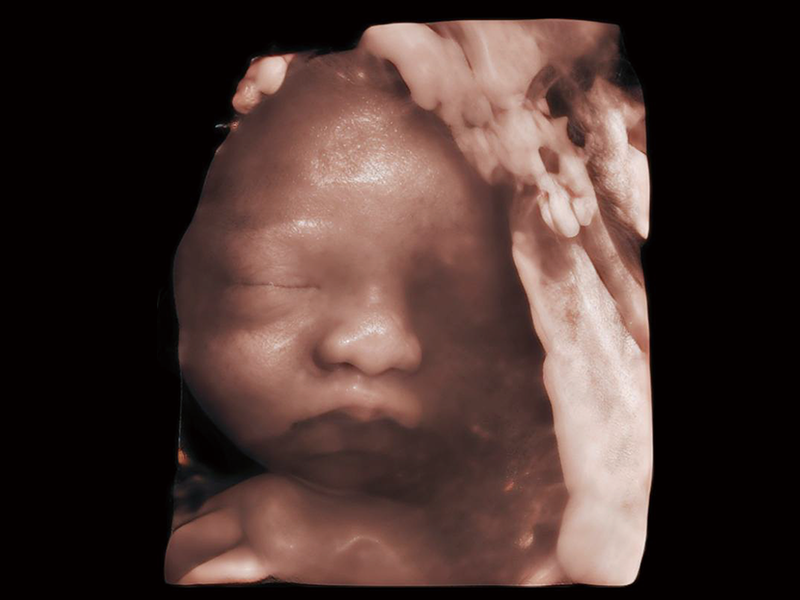

作為開(kāi)立醫(yī)療全新打造的超高端旗艦超聲產(chǎn)品,從探頭抬起喚醒開(kāi)啟掃查到多維探頭發(fā)射接收,通過(guò)先進(jìn)的場(chǎng)成像發(fā)射、自適應(yīng)聚合重建等技術(shù),基于RF Data原始射頻數(shù)據(jù)在圖像生成、高端功能等方面實(shí)現(xiàn)突破,為婦產(chǎn)科、兒科提供全方位臨床解決方案。

夢(mèng)溪?P80以“關(guān)愛(ài)女性”為基石,提供全方位的解決方案,量身定制以滿(mǎn)足女性的健康需求,涵蓋婦科、生殖健康檢查、產(chǎn)前篩查及產(chǎn)后康復(fù)等領(lǐng)域。